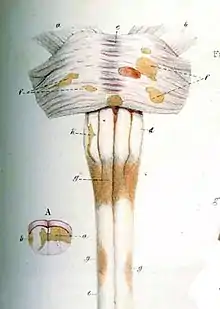

Spinal cord damage

Cervical spinal cord has been found to be affected by MS even without attacks, and damage correlates with disability.[41] In RRMS, cervical spinal cord activity is enhanced, to compensate for the damage of other tissues.[42] It has been shown that Fractional anisotropy of cervical spinal cord is lower than normal, showing that there is damage hidden from normal MRI.[43]

Progressive tissue loss and injury occur in the cervical cord of MS patients. These two components of cord damage are not interrelated, suggesting that a multiparametric MRI approach is needed to get estimates of such a damage. MS cord pathology is independent of brain changes, develops at different rates according to disease phenotype, and is associated to medium-term disability accrual.[44]

Spinal cord presents grey matter lesions, that can be confirmed post-mortem and by high field MR imaging. Spinal cord grey matter lesions may be detected on MRI more readily than GM lesions in the brain, making the cord a promising site to study the grey matter demyelination.[45] Myelin Water Fraction (MWF) shows lesions under MRI[46]

Several CSF markers reveal intrathecal inflammation in progressive MS (SPMS and PPMS)[47]